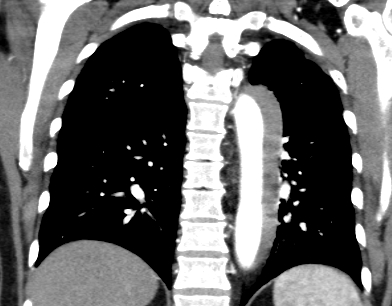

A 70-year-old woman with no cardiovascular history presented with sudden-onset, severe substernal chest pain radiating to the back while doing yard work, associated with diaphoresis, shortness of breath, and right-hand paresthesia. She was a never-smoker and denied alcohol or drug use. At urgent care, her blood pressure was 196/174 mmHg. After receiving aspirin and sublingual nitroglycerin, she was transferred to the ED with persistent back pain (BP 186/110 mmHg). D-dimer was 1.49. ECG showed no ischemia. CTA revealed a Stanford type B aortic dissection extending from the distal arch to the aortic hiatus. She was started on IV esmolol and nicardipine and transferred for vascular surgery evaluation. TTE showed normal LV ejection fraction (65–70%), grade 1 diastolic dysfunction, and moderate concentric LV hypertrophy. She was managed conservatively without surgery, transitioned to oral antihypertensives, and scheduled for surveillance follow-up to monitor for progression.

Initial labs showed elevated hemoglobin (18.2 g/dL) and hematocrit (58.9%), prompting outpatient evaluation. Hematologic workup revealed low erythropoietin (1.8 mIU/mL) and a positive JAK2 V617F mutation, confirming polycythemia vera. She was started on hydroxyurea, low-dose aspirin, and serial phlebotomy. Hematocrit and BP normalized, and repeat CTA at 3 months showed complete resolution of the dissection.